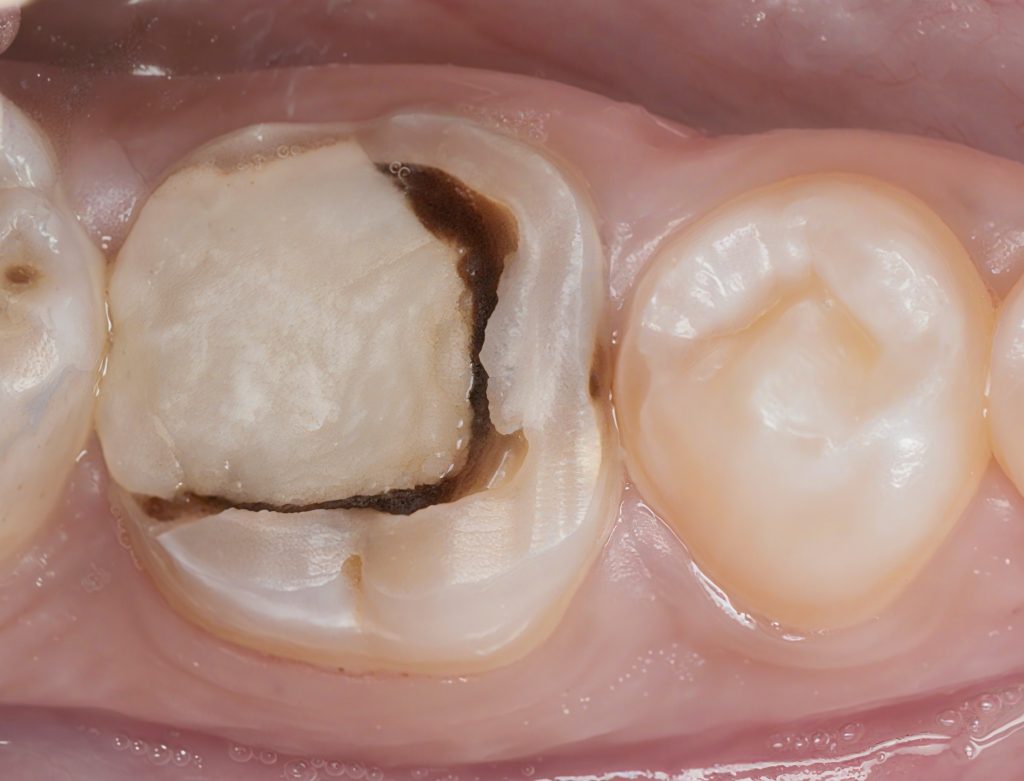

3. Caries Removal & Pulp Chamber Exposure

(Images 4–6)

- Selective caries removal following Fusayama’s principles.

- Preserved affected dentin over pulp.

- Clean DEJ margin created for reliable bonding.

- Pulp chamber fully unroofed and anatomy clarified.